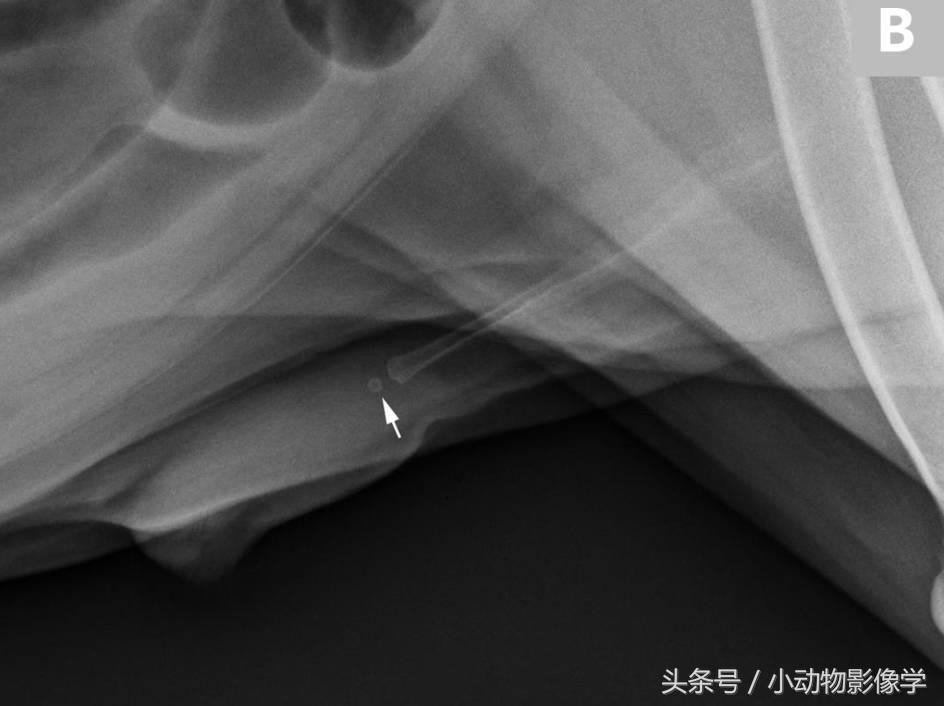

阴茎骨相关的成骨作用的单独中心可能会与尿道结石十分相似(图11A和B)。骨化中心可以出现在阴茎骨的任意一端,且与阴茎骨在同一直线上。尿道海绵体内的结石位于阴茎骨腹侧的尿道部位。对比尿道造影在区分尿道结石和分离的骨化中心会非常有用(图11C)。

图11B、一只公犬的侧位平片,显示阴茎骨头部远端有一块很小的单独的骨化中心(箭头)。